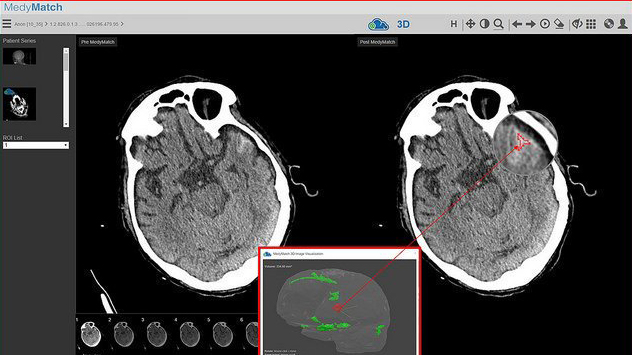

IBM Watson Health and Israel-based MedyMatch Technology are joining their AI forces in hospital emergency rooms to help doctors detect intracranial bleeding resulting from head trauma and stroke.

MedyMatch Technology and Samsung NeuroLogica have teamed up to help paramedics and EMTs more quickly and accurately assess stroke patients in prehospital environments.